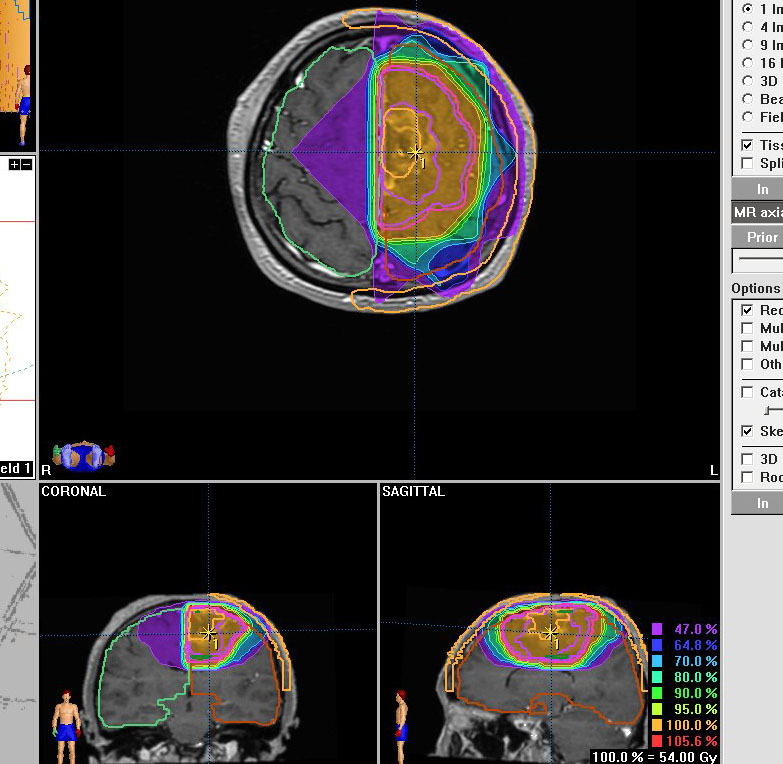

40代の患者さんです。夜間睡眠中の全般発作(症候性てんかん)で発症しました。フレア画像で左上前頭回に滲むような高信号領域(白い部分)がみられます。右側はガドリニウム増強MRIですが,全く増強されません。グレード2か3の星細胞腫あるいは乏突起膠腫を疑います。白く滲むような領域はよく見るとかなり広範囲に広がっています。

画像上では全摘出 gross total removalできて,病理診断は,退形成性乏突起星細胞腫 anaplastic oligoastrocytomaでした。IDH変異あり,1p/19q欠失なしです。現在の診断なら,退形成性星細胞腫 グレード3です。

手術後に54グレイの広範囲な局所放射線治療とテモゾロマイド化学療法を行いました。左の画像は放射線治療計画の時の線量分布図です。

5年後にいきなり激しい再発を生じました。再発部位は,放射線照射野外 out-of-fieldの前頭部帯状回でした。手術前に急速に増大して,画像所見も初回と全く違いました。摘出後の病理は,IDH1/2 wild type, 1p/19q intact, ATRX negative, MGMT met negative, MIB-1 40%という典型的な膠芽腫の所見でした。

この例とは異なって,退形成性星細胞腫の再発時には,IDH mutantのままの方が多いです。もしかすると先行した放射線誘発膠芽腫かもしれません。